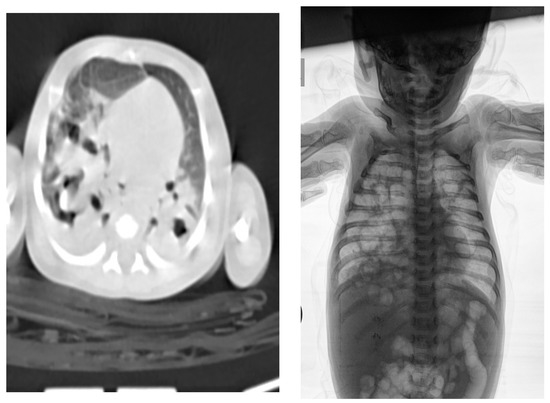

| Clinical picture at admission in Pediatric Clinic UCC | NN1 had a preserved sensorium, was high febrile 39.4 °C (rectal), with tachy-dyspnea, sobs, and moans, indents jugulum, dissatisfied cries, TM 4050 g, subclinical jaundice of the skin, and visible mucosa. Auscultation revealed attenuated respiratory sound, diffusely fine crackles, SaO2 82%, R 56/min, F 196/min. The umbilical stump persisted, the surrounding skin became red and swollen, there was hypotonia of the body axis, large fontanelle within the bony borders, greatness 20 × 30 mm. The other physical findings were normal. | NN2 had the preserved sensorium, was afebrile 37.7 °C (rectal), TM 3920 g, eupnoeic, presented sobs and moans, plethoric and icteric skin, nasal vestibules filled with seromucous secretion, and hyperemic throat. Auscultatory revealed a normal breathing sound is heard with transmitted wheezes from the upper parts of the airways and systolic murmur of 1-2/6 according to Levin, SaO2 97%, R 32/min, F 168/min. The umbilical stump persisted, thin, and the borders developed a serous–hemorrhagic discharge. There was mild hypotonia of the shoulder girdle and trunk axis, primitive reflexes were slowly elicited, large fontanelle was below the plane of the bony borders, and slightly spaced sutures, greatness 40 × 40 mm. The other physical findings were normal. |